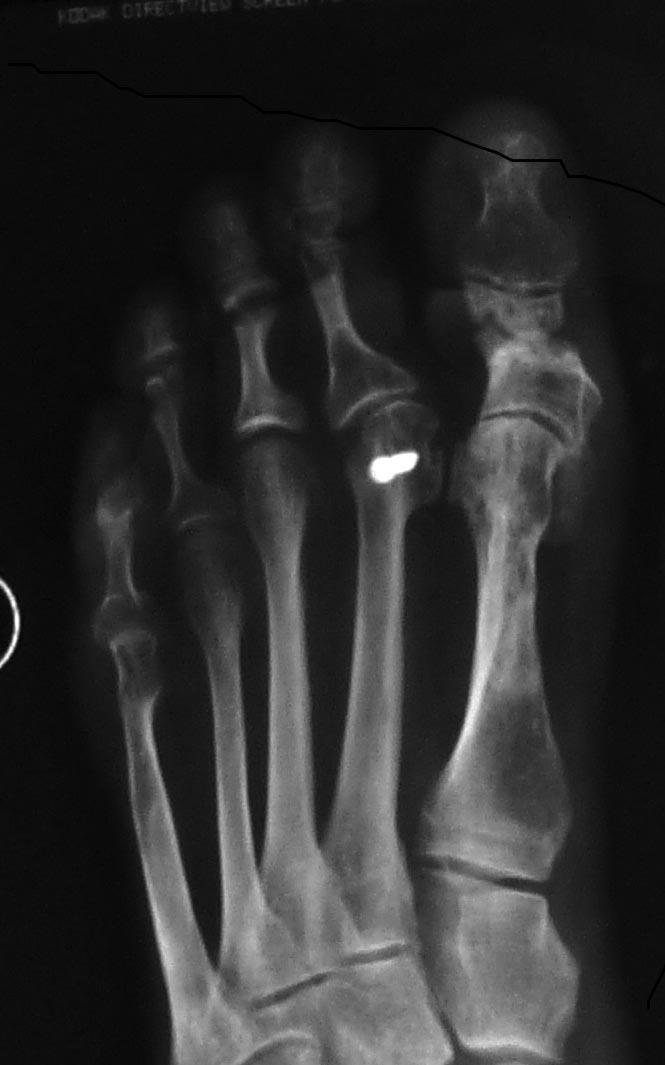

И чтобы закончить тему scarf "по любому случаю" - рентгенограмма с

вчерашней консультации. Пациентка оперирована 5 лет назад известным

хирургом. Scarf при маленьком М1М2 (при отсутствии первичных снимков это

легко представить по ориентации основания М1 и углу наклона суставных

поверхностей первого плюснеклиновидного сустава). Одно из последствий

операции - неоартроз между головками М1 и М2. Я такое впервые увидел.